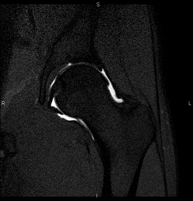

- Artro-RM Cadera

Exploración para el estudio de las lesiones en pequeñas estructuras anatómicas de la articulación que suelen lesionarse en pacientes que sufren luxación o pinzamiento (disminución del espacio). El estudio viene precedido por una inyección de contraste en el interior de la articulación, realizada bajo control de rayos X. La duración global de los dos procedimientos es de 50 minutos.